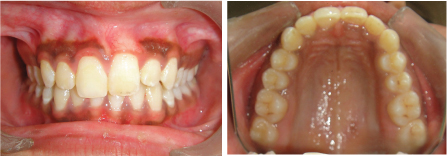

A 12-year-old female patient reported to the Department of Orthodontics of Maulana Azad Institute of Dental Sciences, New Delhi with chief complaint of missing upper front tooth. On clinical examination it was found that maxillary left central incisor (21) was missing [Table/Fig-1]. No significant history of trauma or premature/delayed shedding of primary left central incisor was reported. Panoramic and maxillary occlusal view revealed impacted left central incisor with dilacerated root [Table/Fig-2,3]. Since the contralateral central incisor had erupted fully in the mouth and the root formation of the impacted central incisor was almost complete, it was decided to disimpact the tooth (21). Disimpaction was planned by surgical exposure followed by elastic traction with the help of removable appliance. Since the patient had well aligned upper and lower arches in good occlusion, it was decided to use a modified removable appliance for extrusion of 21. A removable appliance with modified labial bow was fabricated. Labial bow in the anterior region was fabricated with 22 gauge wire and helices were incorporated in the labial bow adjacent to left central incisor region. Retention was provided by the acrylic coverage in the palatal region and by well formed retentive clasps. Surgical exposure of left central incisor was performed by open exposure technique. A bondable button was placed onto the labial surface of exposed left central incisor crown [Table/Fig-4]. Patient was trained to use elastic in triangular fashion to engage button on 21, and two helices of the labial bow, which resulted in an extrusive force of 20 grams for disimpaction of 21[Table/Fig-5] [1]. Patient was advised to change the elastic daily and was reviewed every three weeks. At the end of six months, complete disimpaction of 21 was achieved with the tooth in its optimal alignment into the upper dental arch and in good relation with lower teeth [Table/Fig-6,7]. Post disimpaction panoramic view reveals tooth 21 in the optimal position with respect to maxillary occlusal plane [Table/Fig-8].

Pretreatment intraoral maxillary occlusal photograph showing missing maxillary left central incisor.

Post treatment intraoral frontal and maxillary occlusal photographs showing 21 in alignment and good occlusion.